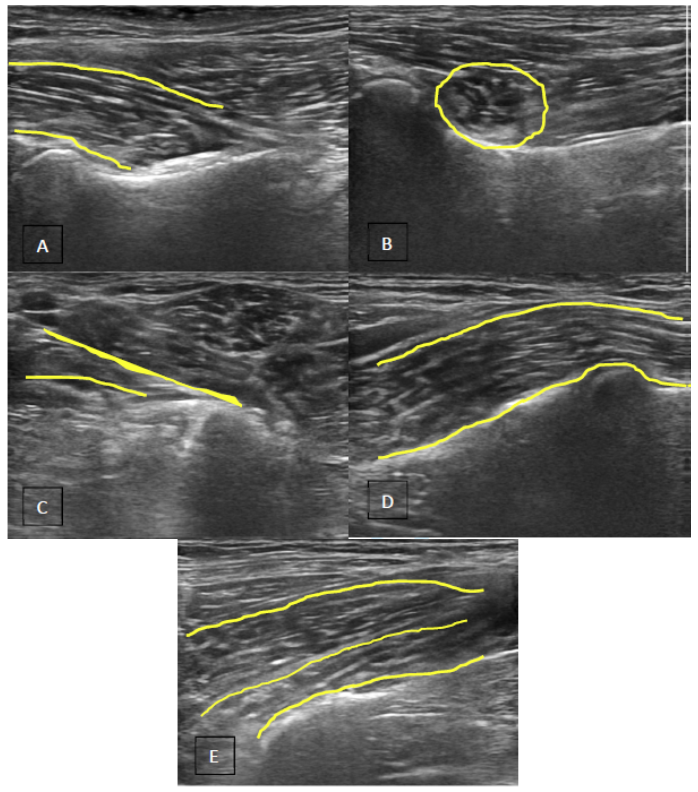

Objective: Iliopsoas injury and strain is a commonly diagnosed disease process, especially amongst working and sporting canines. There has been very little published literature regarding iliopsoas injuries and there is no information regarding the ultrasound evaluation of abnormal iliopsoas muscles. This manuscript is intended to describe the ultrasound findings in 73 canine agility athletes who had physical examination findings consistent with iliopsoas discomfort. The population was chosen given the high incidence of these animals for the development of iliopsoas injury; likely due to repetitive stress.

Methods: Medical records of 73 agility performance canines that underwent musculoskeletal ultrasound evaluation of bilateral iliopsoas muscle groups were retrospectively reviewed. Data included signalment, previous radiographic findings, and ultrasound findings. A 3-tier grading scheme for acute strains was used while the practitioner also evaluated for evidence of chronic injury and bursitis.

Results: The majority of pathologies were localised to the tendon of insertion, with the majority being low grade I-II strains (80.8%). Tendon fibre disruption (71.2%) and indistinct hypoechoic lesions (91.8%) were the most common of acute changes noted. Hyperechoic chronic changes were noted in 84.9 percent of cases. Acute and chronic changes were commonly seen together (62.8%).

Conclusion: Diagnostic musculoskeletal ultrasound was used to identify lesions of the iliopsoas tendon consistent with acute and chronic injury, as well as identifying the region of pathology. The majority of agility performance dogs had low grade acute strains based on the tiered system, with mixed acute and chronic lesions being noted frequently.

Application: Diagnostic musculoskeletal ultrasound provides a non-invasive diagnostic modality for patients suspected of having an iliopsoas strain.